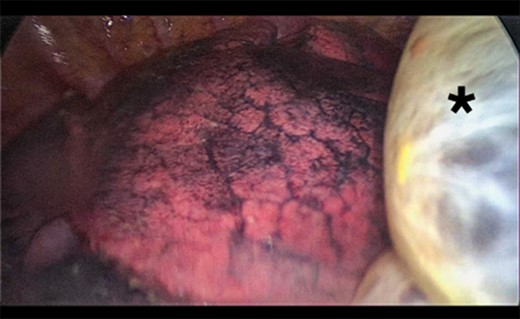

A 73-year-old male patient with a clinical history of COPD, lung emphysema and a 30-year smoking history was admitted to the ED due to a 24-h clinical picture of dyspnea immediately following a sudden bout of dry coughing. Physical examination showed a dyspneic patient, tachypnea of 25 rpm, heart rate of 85 bpm and blood Pressure of 135/75 mmHg along with central cyanosis. Chest exam showed a hyper-resonant right hemithorax along with reduced breath sounds. Initial chest X-ray revealed a large right-sided pneumothorax (Fig. 1). A right chest tube was placed in the ED. Emergency echocardiogram had no significant findings and spirometry showed suspected patterns of obstruction. Following patient stabilization, a high-resolution chest computed tomography (HRCT) was performed revealing extensive pan lobar emphysema throughout both lungs, para septal emphysema in both the anterior upper lobes and herniation of a left lung bullae through the anterior mediastinal pleura along with a right-sided pneumothorax with the chest tube in place with persistent air space (Fig. 2). The patient was taken to surgery where a right video-assisted thoracoscopic (VATS) approach showed severe lung emphysema and a contralateral herniated left lung bulla through the mediastinal pleura anterior to the pericardium (Fig. 3). Right pleurodesis was performed using Talc and a left posterior thoracoscopy showed a severe emphysematous left lung with a lingular herniated bulla to the right hemithorax through an anterior mediastinal pleural defect along with pleural adhesions (Figs 4 and 5). Thoracoscopic hernia reduction was performed along with bullectomy using 60 mm mechanical sutures (Fig. 6). Chest tubes were removed on POD 3 (right) and POD 4 (left). The patient had significant respiratory improvement and was discharged on POD 5.

Thoracoscopic view of transmediasinal herniation of pulmonary bulla to the right hemithorax (asterisk).